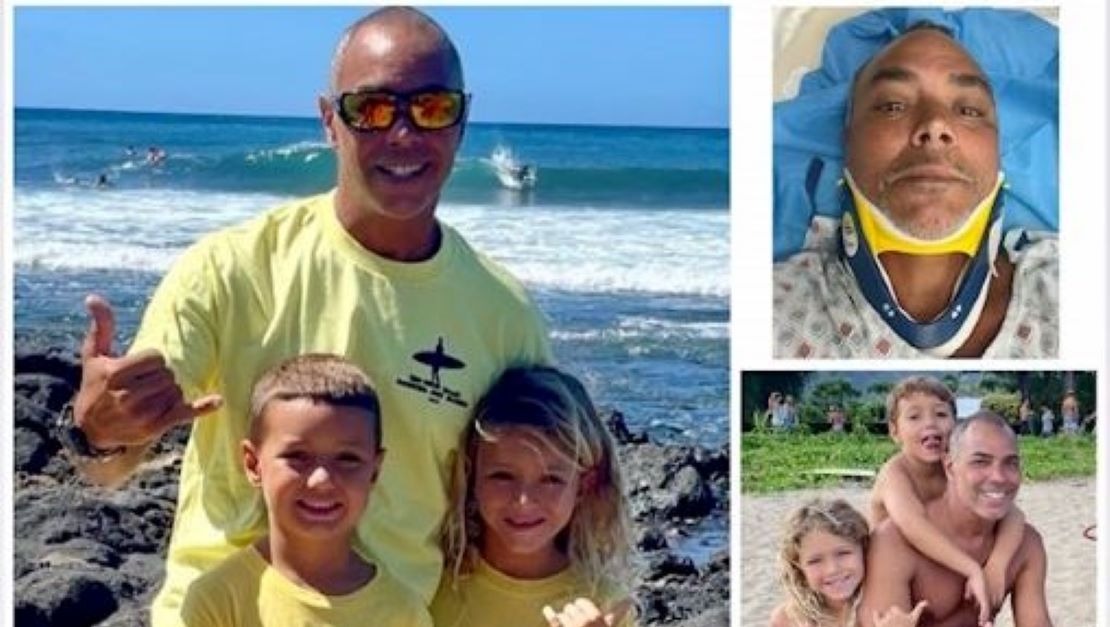

The man is a gentleman and does a ton for his two boys. He was injured surfing by someone dropping in and then losing his board and the board hitting him in the back of the neck. His neck was broken in 4 places and he will be unable to work for 3 months at the very least. He does so much for the surf scene on Kaua'i, is an ambassador of Aloha and needs our help to provide for his boys.

I teach in Kapa'a and all the kids know and love him. He is always spreading joy and stoke.

"Yesterday while surfing Hanalei a loose longboard hit me in the back of my head and broke my neck. I was helping an unko that had lost his board when it happened. The pain was indescribable. I thought I was done. I screamed in pain, held my neck with my left hand and paddled with my right arm. My whole life flashed in front of me and all I thought about was my Zboyz. I just kept going towards the beach, screaming for help n no one helped til I got to the shore. Luckily I knew a guy (I forget his name) carried me to the dry sand. I was lucky once again. People, please use a leash and stop hurting others in the lineup. From Pakalas to Hanalei, please think of others. The life you save may not be your own."